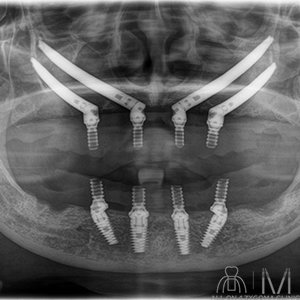

両側上顎は前臼歯歯槽骨に十分なボリュームがないが、頬側に十分なスペースの確保が見込めた。下顎は菲薄な部位はあるものの5┬5を骨整形する事で十分な骨幅の確保が見込めると判断し、この部位に4本ノーマルインプラント埋入予定とした。前歯~小臼歯部で歯槽堤の高低差が大きいことから、安定度を高めるプラットフォームの設計が必要であると考えた。また、頬骨に十分な厚みがある事からザイゴマインプラント4本を用いる上下顎All-on-4治療 を計画した。手術を円滑なものとする為、術中は静脈内鎮静法下での手術を予定した。